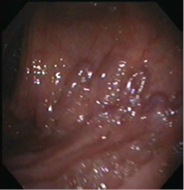

La videoendoscopia digestiva alta informa gastritis erosiva leve, sin signos de sangrado activo. La videocolonoscopia muestra desde el ciego hasta el colon descendente cordón venoso azulado, tortuoso y prominente que disminuye con la insuflación, sin evidencia de sangrado activo.

Diagnóstico: várices colónicas con afectación predominante del colon derecho, transverso y descendente. (Fig. 1 A y B)

Figura 1. Videocolonoscopía. Se observan las várices colónicas tortuosas en la submucosa. A. Lesiones de aspecto nodular. B. Vasos serpiginosos.